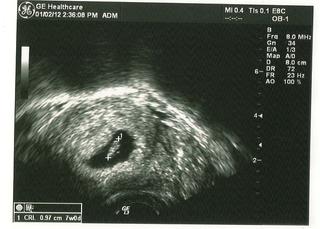

Ahoj holky, tak som dnes bola na kontrole a utz. Vsetko je v poriadku, nasa fazolka ma 9,7 mm a bolo vidiet srdiecko. Krasne tam skakalo. Krasny pohlad to bol. Prikladam fotecku.

@mijadave Janka, prosim, kedze kontrola dopadla dobre a je srdiecko, mozes ma prehodit do dolnej tabulky. Doktorka to vypocitala na 7+3. Kontrolu mam 16.1.